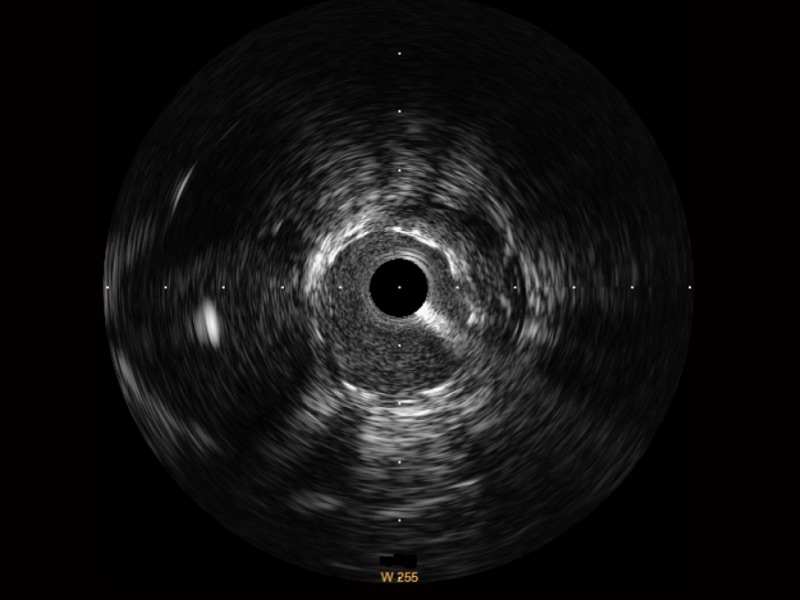

• 银河集团官网宽频IVUS图像

• 传统IVUS图像

对比传统IVUS导管成像,银河集团官网宽频IVUS图像的近场支架梁显影更细腻,远场中膜外血管仍清晰可辨,兼顾远中近,兼顾分辨力与穿透深度